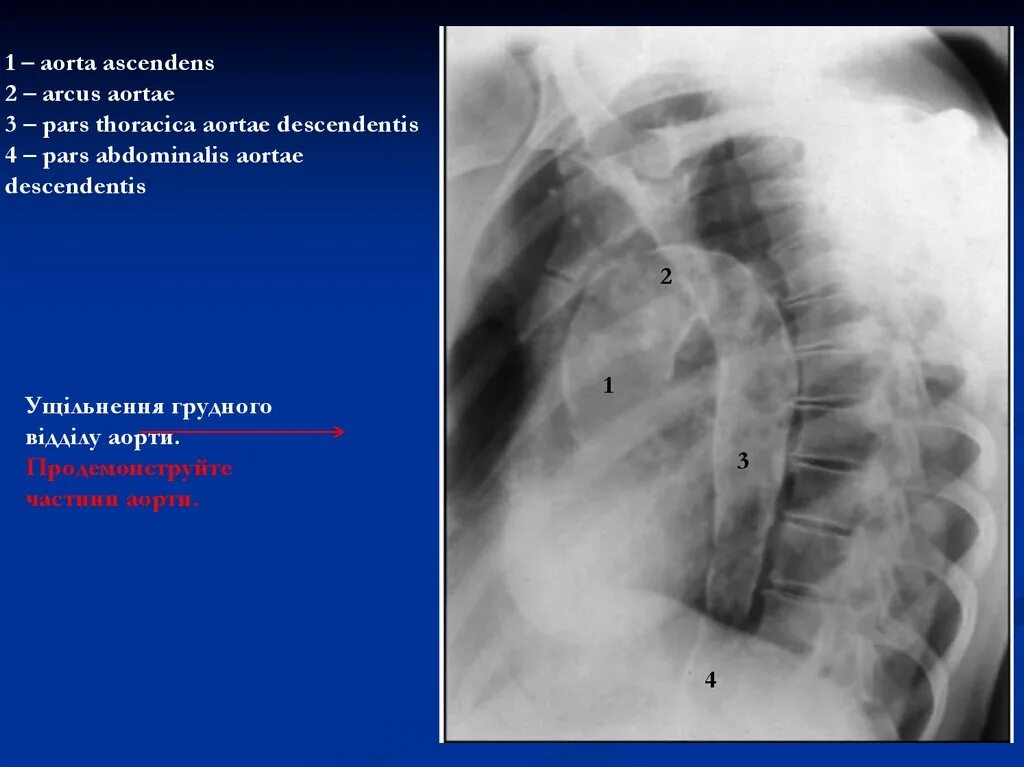

Что значит аорта уплотнена на флюорографии